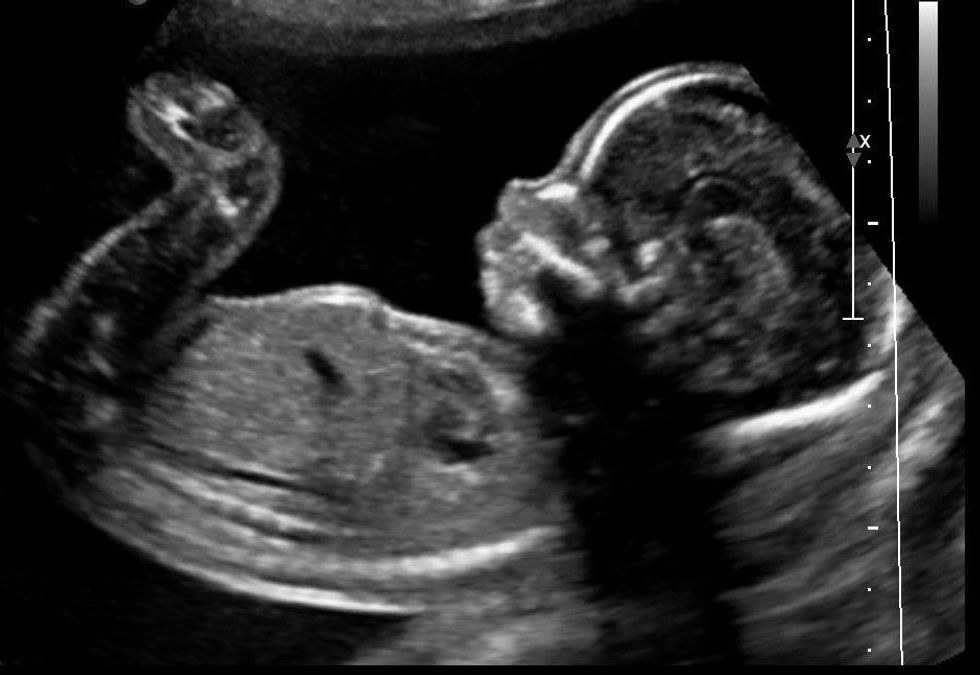

Dr. Dianne N. Irving’s article, “When Do Human Beings Begin?” from Princeton University’s International Journal of Sociology and Social Policy states that when fertilization begins, parts of human beings have been changed into a whole human being. “During the process of fertilization, the sperm and the oocyte cease to exist as such, and a new human being is produced.” This author, as well as many other scholars and experts, have agreed on this undeniable fact. With that being said, in any situation, one must consider the fact that the life or death of a being should not be determined by the size, level of development, environment, or dependency.

Can we say that it is reasonable for a 5-year-old to be murdered because of what we think he is going to become, or the current financial situation he is in? Doing so would assume that we can take away from the fact that the 5-year-old is a living being with his or her own rights. If the live being inside of a women’s stomach is alive just as well, then we must not rob that person of his or her rights based on the circumstances mentioned earlier. Doing so directly contradicts one of our most fundamental human rights, the right to life.